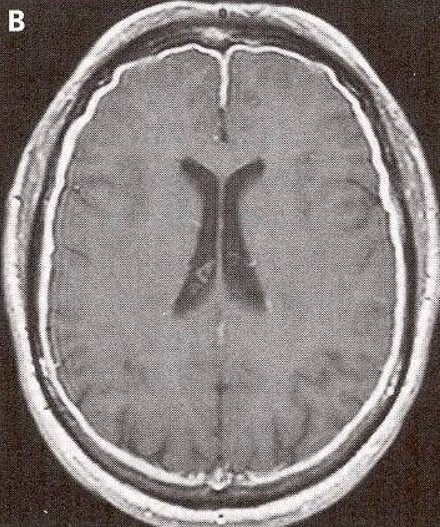

You are rotating on your radiology rotation and are asked to interpret an MRI

(gadolinium enhanced) in a 55-year-old man who is complaining of a persistent headache

and pain in his jaw when he eats.

DIAGNOSIS: Pachymeningitis.

Dural thickening (white margin) is evident in this MRI of the brain.